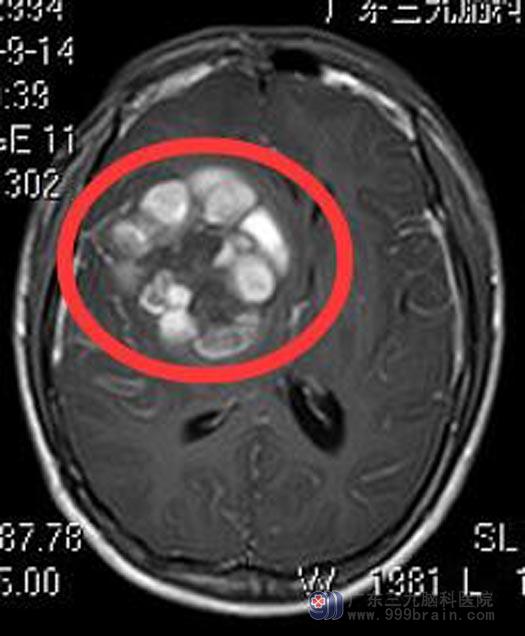

小杰今年18岁,一周前出现头痛,伴间断呕吐,当地医院头颅CT检查提示:右侧颞叶基底节区出血。广东三九脑科医院头颅MR检查提示:右侧基底节区为主占位性病变,结合SWI(磁敏感加权成像)检查考虑巨大海绵状血管瘤伴出血。

经综合神经外科鲁明主任详细讲解病情后,家属要求手术治疗。鲁明主任主刀,在全麻唤醒麻醉下行右侧额叶、基底节区巨大海绵状血管瘤切除术。术中唤醒病人,导航定位,见侧裂大脑中动脉分支,进入深度约3.0cm见黄色异常脑组织,造瘘见内含陈旧性暗红色血块,血块中夹杂灰色血管网状异常血管团,血供丰富,与周围脑组织间有一层淡黄色稀烂样组织,镜下全切除异常组织,患者语言、肢体功能正常。术后小杰康复很快,已满意出院。术后病理结果:海绵状血管瘤。